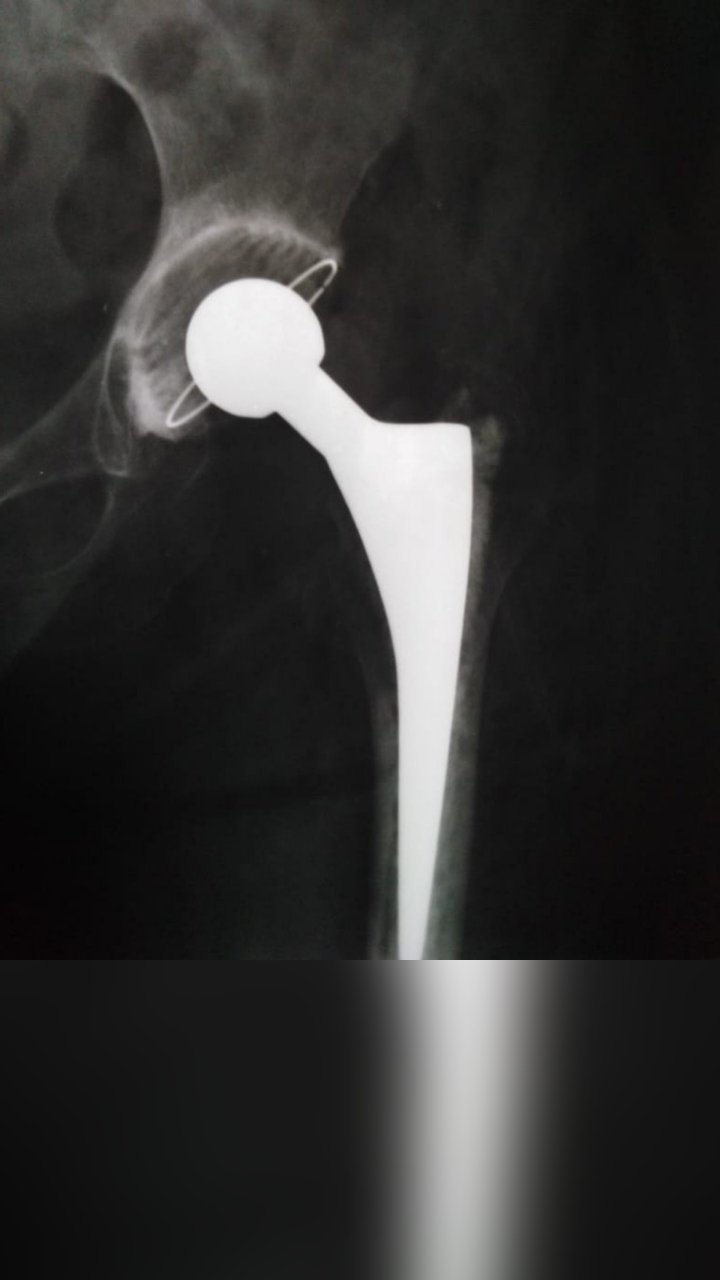

TOTAL HIP REPLACEMENT